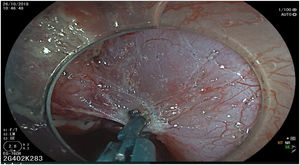

The endoscopic classification utilized to diagnose all lesions included in the present study was the Paris classification, whose validity is widely accepted by the different international consensuses and clinical guidelines. The following techniques were employed in the present study for the detection and characterization of the gastric lesions as follows: High-resolution white light endoscopy associated with a detailed and systematic review of the integrity of the gastric mucosa was initially utilized to identify lesions (Fig. 1). FICE (Flexible Spectral Imaging Colour Enhancement, Fujifilm Co., Japan) virtual chromoendoscopy or chromoendoscopy with 0.4% indigo carmine contrast staining were then employed to better characterize and delimit the lesions found (Fig. 2). In some cases, to optimize the evaluation of gastric abnormalities found (emphasizing special details, such as determining the microvascular pattern and specific alterations of the microsurface of the mucosa), minimum endoscopic image magnification, together with LCI (Linked Color Imaging, Fujifilm Co., Japan) and BLI (Blue Laser Imaging, Fujifilm Co., Japan) virtual chromoendoscopy, was utilized to show the demarcation line of the neoplastic lesion (Fig. 3), as well as microvascularization alterations (Fig. 4).

All the patients were treated by the same endoscopist (VA), who is one of the pioneers in ESD in Latin America. He received formal theoretic and practical training in Japan, visiting internationally recognized endoscopy centers, where he had numerous opportunities to assist experts in procedures on humans and perform ESD under supervision on animal models. In addition, he has participated as the lead researcher in different studies on ESD. Briefly, the ESD technique employed was the following: a therapeutic gastroscope with a 3.2mm working channel (450 RD, Fujifilm Co., Japan), the 2.0 or 2.5 BT Flush Knife (Fujifilm Co., Japan) connected to the electrosurgical unit (ERBE VIO 200S, 200D, or 300D, Tubingen, Germany), and a 4mm long cap on the tip of the equipment (Top Co., Japan) were utilized to for better visualization in the dissection field. The following steps were employed: Demarcation, Soft coagulation mode, Effect 6, 100W; Mucosal incision: Endocut I, Effect 2, Cut length 3, Cut interval 2; Submucosal dissection: Forced coagulation mode, Effect 3, 50W; Pre-hemostasis of the vessels: Soft coagulation mode, Effect 6, 100W. Vessel hemostasis was carried out using the same Flush Knife and the coagulation grasper was used for larger vessels (Coag Grasper, Olympus Co., Japan). In 75.7% of the endoscopic dissections performed, the teardrop presentation of sodium hyaluronate at 0.4% (Adaptis Fresh®, Legrand Laboratory, Brazil) was the substance used for submucosal injection at a mean solution volume of 10cm3 per patient and at an additional cost of 10 USD per procedure. Other substances used were mannitol (9.7% of the cases), hydroxypropyl methylcellulose (8.7%), and saline solution (3.8%). Figs. 1–10 show the technique employed at each step of the procedure in the present study.